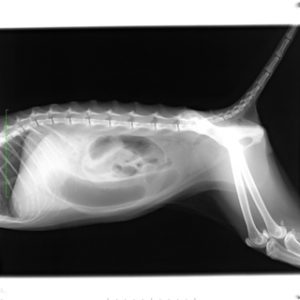

左が横向きの画像、右が仰向けの画像です。

レントゲン検査では、「小腸の拡張」「大小不同」が認められます。ソーセージ状にみえる黒い所は、小腸内に貯留した「ガス」です。

消化管は、言葉が示すように管(くだ)ですから、ある部分に多量にかつ腸管壁を押し広げるようにガスが溜まることは、不可能です。

絶対に、前後に移動してしますはずです。

ガスが貯留し、消化管が拡張しているということは消化管の運動機能低下や閉塞が疑われます。

腸には、小腸と大腸があることはご存知の方も多いと思います。

言葉どおり小腸は小さい(細い)腸です。しかし、レントゲンには大腸よりも大きく拡張した小腸が写っています。